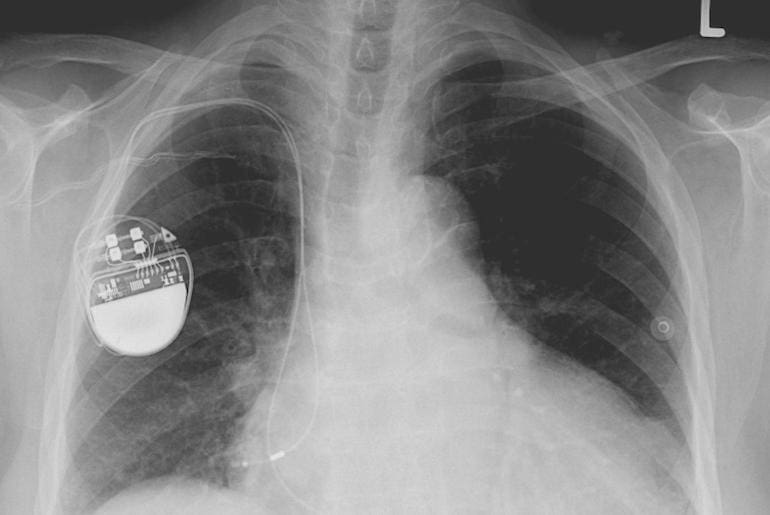

Fridays in the House of Commons are reserved for private members bills when MPs can raise issues on behalf of their constituents or other groups. For example, the bill to make life-saving first aid education compulsory in secondary schools was supported by St John Ambulance and the British Red Cross, and built on campaign work done by the British Heart Foundation over a number of years. However, limited time is allowed for debate, meaning that if the speeches are still going on when the clock strikes, then there is no time for a vote and the bill gets shelved.